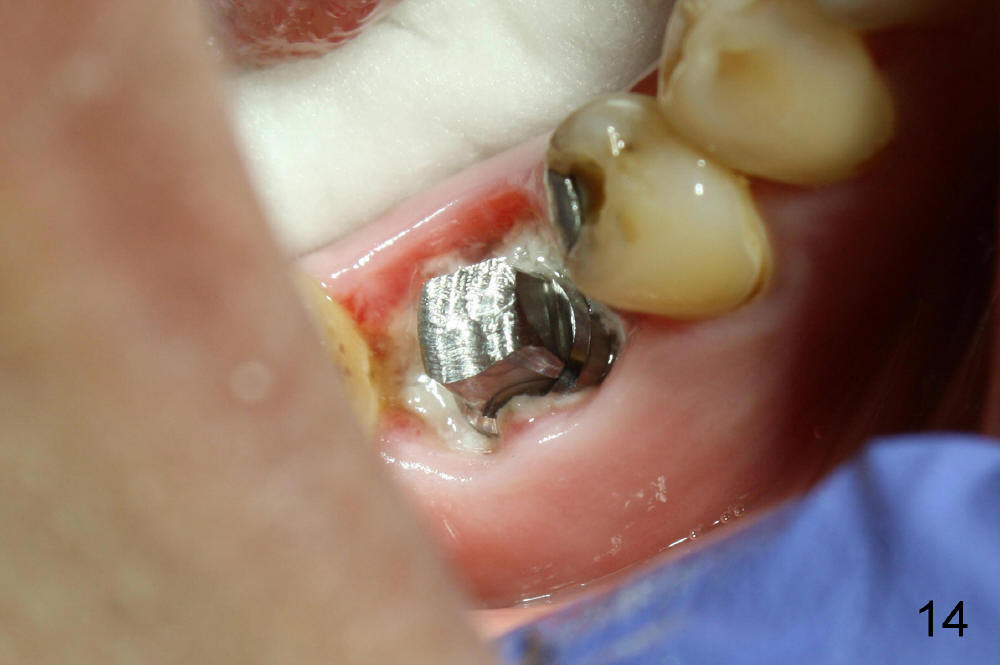

A 38-year-old lady agrees to have implant placement 7 years after loss of the crown of the lower right first molar (Fig.1,2). When the tooth is extracted, the septum is found to be low (Fig.3,4). To confirm it, a PA is taken (Fig.5). To initiate an osteotomy in the septum, it is trans-sectioned with thin osteotomes as shown in Fig.4 insert (black line). A 2 mm pilot drill is placed in the septum (Fig.6: P). The osteotomy is enlarged by 2.5-4.0 mm reamers (Fig.7,8), followed by insertion of 6x17 mm tapered tap at the depth 14 mm (Fig.9). The osteotomy is further enlarged by 4.5 and 5.0 mm reamers. A 6.0x14 mm one piece implant is placed initially. The trajectory is not ideal. A 6.0x14 mm one piece implant is placed initially. The trajectory is not ideal. The implant is removed from the osteotomy partially and reinserted with improved trajectory (Fig.11, compare to Fig.10 (red line)). Primary stability is high. There is not much bone mesiodistally so that the trajectory is easily changed in that direction. After abutment preparation, mixture of autogenous bone (harvested from reamers) and allograft is placed in the residual mesial and distal sockets (Fig.12). To contain the bone graft, an immediate provisional is placed (Fig.13 P). The occlusal plane of the provisional is significantly lower than that of the adjacent teeth to avoid micromovement of the implant. The patient is advised to eat soft food on the left side. Six days postop, the patient returns for prophy. The provisional is removed; the bone graft appears to be incorporating into the socket (Fig.14). After recementation, the provisional remains in place for 3.5 months; PA shows increased bone density in the mesial and distal sockets (Fig.15, compare to Fig.5,11). Due to insurance coverage, the patient defers fabrication of definitive restoration for at least 7 months. The immediate provisional is finally lost 8.5 months postop: the gingiva attaches to the 1-piece implant (Fig.16), while the density of the mesial socket increases (Fig.17 *) with formation of the cortex (lamina dura) coronally (v). Before the provisional (Fig.18 P) is removed for cementation of the definitive restoration, black shadow (*) is noted over the buccal gingiva. It is partially due to buccal placement (Fig.19) and partially due to buccal atrophy over a period of 10.5 months postop. How to prevent buccal placement? Positioning the first pilot drill in the septum buccolingually is a key. Eleven months post crown (Fig.20 C) cementation, the black shadow remains, but there is no tenderness. If the implant threads are immediately underneath the periosteum, there is tenderness.